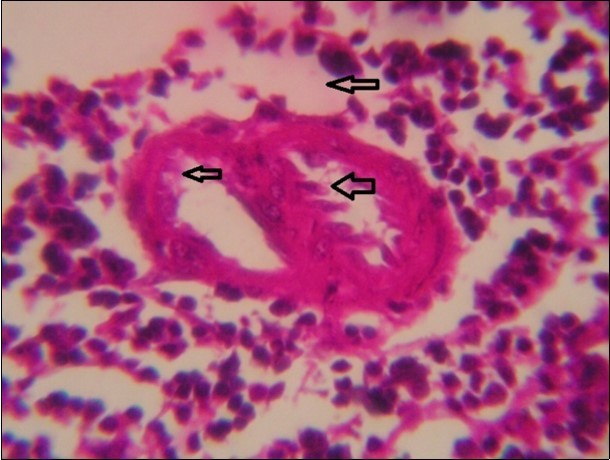

Figure 8.spleen (dead cattle less than 1 year old) showed severe depletion of lymphocytes with necrosis of endothelial lining or splenic arterioles (arrows). (Hematoxylin and fuchsin X 60)